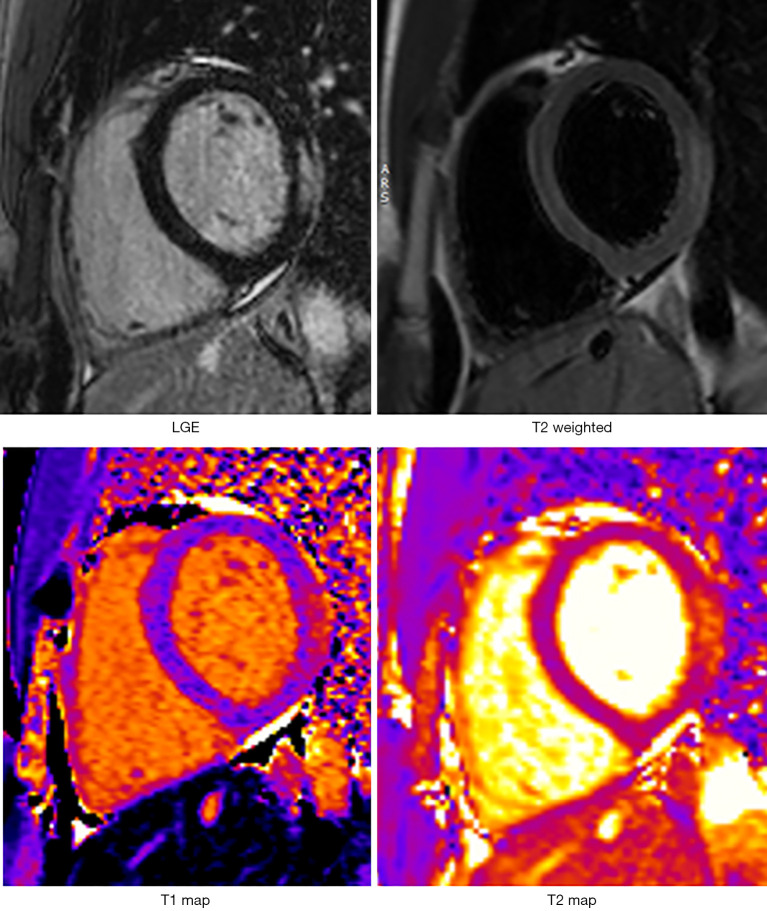

Cardiac magnetic resonance (CMR) imaging has become a crucial diagnostic and prognostic tool for assessing myocardial health, especially in pediatric patients with congenital heart disease. This review focuses on the role of CMR in myocardial tissue characterization, particularly its ability to detect and quantify fibrosis using techniques such as late gadolinium enhancement (LGE), T1 and T2 mapping, and extra-cellular volume (ECV) measurements. CMR offers superior anatomical and functional information, complementing traditional imaging modalities by enabling detailed visualization of native myocardial edema, interstitial fibrosis, and other tissue changes. These advanced imaging techniques are particularly useful in diagnosing conditions such as myocarditis, cardiac allograft rejection, Kawasaki disease (KD), and other cardiomyopathic processes. In pediatric myocarditis, CMR has demonstrated strong diagnostic utility, with T1 and ECV values helping to differentiate between healthy controls and patients with acute myocarditis, while also predicting disease severity and outcomes. In the context of cardiac transplant, T1 mapping, shows promise in detecting early signs of rejection, providing a less invasive alternative to endomyocardial biopsy. Additionally, CMR has been employed to monitor myocardial damage in KD, where it detects increased ECV in both coronary-affected and remote myocardial areas. The review also discusses CMR's application in tracking myocardial fibrosis in pediatric cardiomyopathies, highlighting its potential as a prognostic marker for heart failure progression. Despite its advantages, challenges remain in standardizing imaging protocols across disease states and establishing comprehensive guidelines for routine use. The future of CMR in pediatric cardiology lies in its ability to improve early diagnosis, guide personalized treatment, and enhance long-term monitoring of heart conditions, ultimately improving patient outcomes.